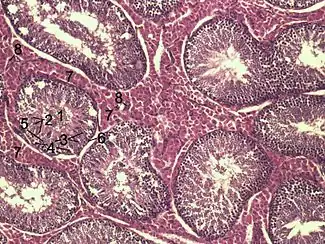

![]() Histological section through testicular parenchyma of a boar. 1 Lumen of Tubulus seminiferus contortus, 2 spermatids, 3 spermatocytes, 4 spermatogonia, 5 Sertoli cell, 6 myofibroblasts, 7 Leydig cells, 8 capillaries | |